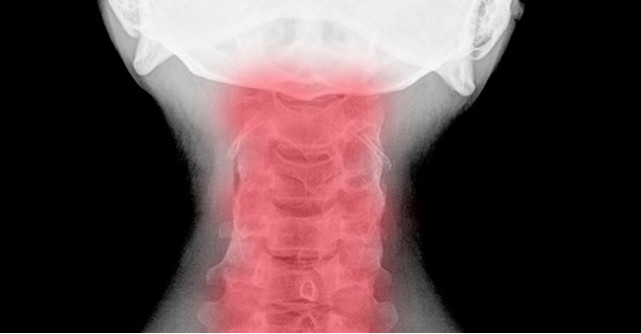

Spondiloza cervicala se caracterizeaza printr-o degenerescenta a coloanei vertebrale, astfel incat apar modificari la nivelul articulatiilor dintre vertebre (discuri vertebrale), la nivelul formei vertebrelor, astfel incat, prin evolutie, se pot forma ciocuri la nivelul coloanei gatului (osteofite) si de asemenea spatiile de iesire a nervilor paravertebrali se pot ingusta, la fel si canalul medular.

spondiloza cervicala